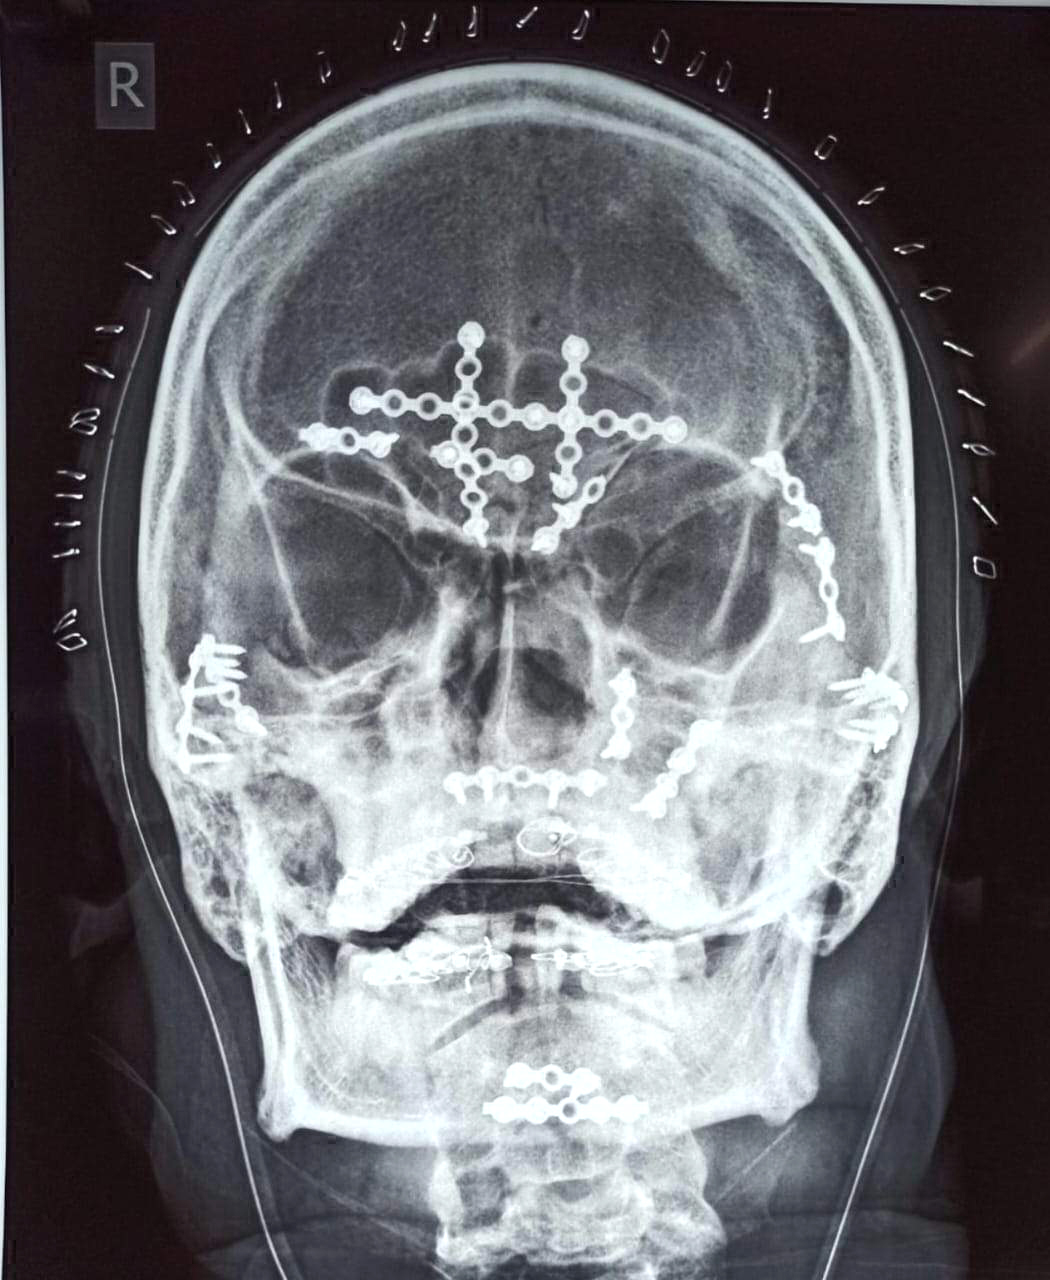

बिलासपुर, 6 मार्च। सड़क दुर्घटना में घायल 40 वर्षीय समीर के माथे की हड्डी, नाक, ऊपरी हड्डी और निचले जबड़े की हड्डी कई टुकड़ों में चूर हो गई थी। सिम्स मेडिकल कॉलेज के डॉक्टरों ने करीब 8 घंटे का ऑपरेशन कर उसके विक्षत चेहरे को फिर से जोड़ दिया।

काठा कोनी के रहने वाले समीर नाम के युवक का सिर और चेहरा सड़क दुर्घटना में चूर चूर हो गया था। दंत रोग के विभाग अध्यक्ष डॉक्टर संदीप प्रकाश ने जरूरी परीक्षण और जांच के बाद उसके ऑपरेशन कर निर्णय लिया। बीते 3 मार्च को समीर का 7 से 8 घंटे तक ऑपरेशन किया गया, उसके चेहरे को फिर से जोड़ा गया। चेहरे को बचाने के लिए टूटी हड्डियों को सुव्यवस्थित करके प्लेटिंग की गई, फिर मुंह के अंदर सिर के ऊपर और एक कान से दूसरे कान तक चीरा और टांका लगाया गया। यह सिम्स की सबसे जटिल सर्जरी में से एक थी। खास बात यह है कि चेहरे पर एक भी चीरा नहीं लगाया गया है, इससे चेहरा खराब नहीं हुआ है। इससे उसे सामान्य जीवन जीने में मदद मिलेगी। सड़क दुर्घटना से समीर के चेहरे की 10 हड्डियां टूटी थी।